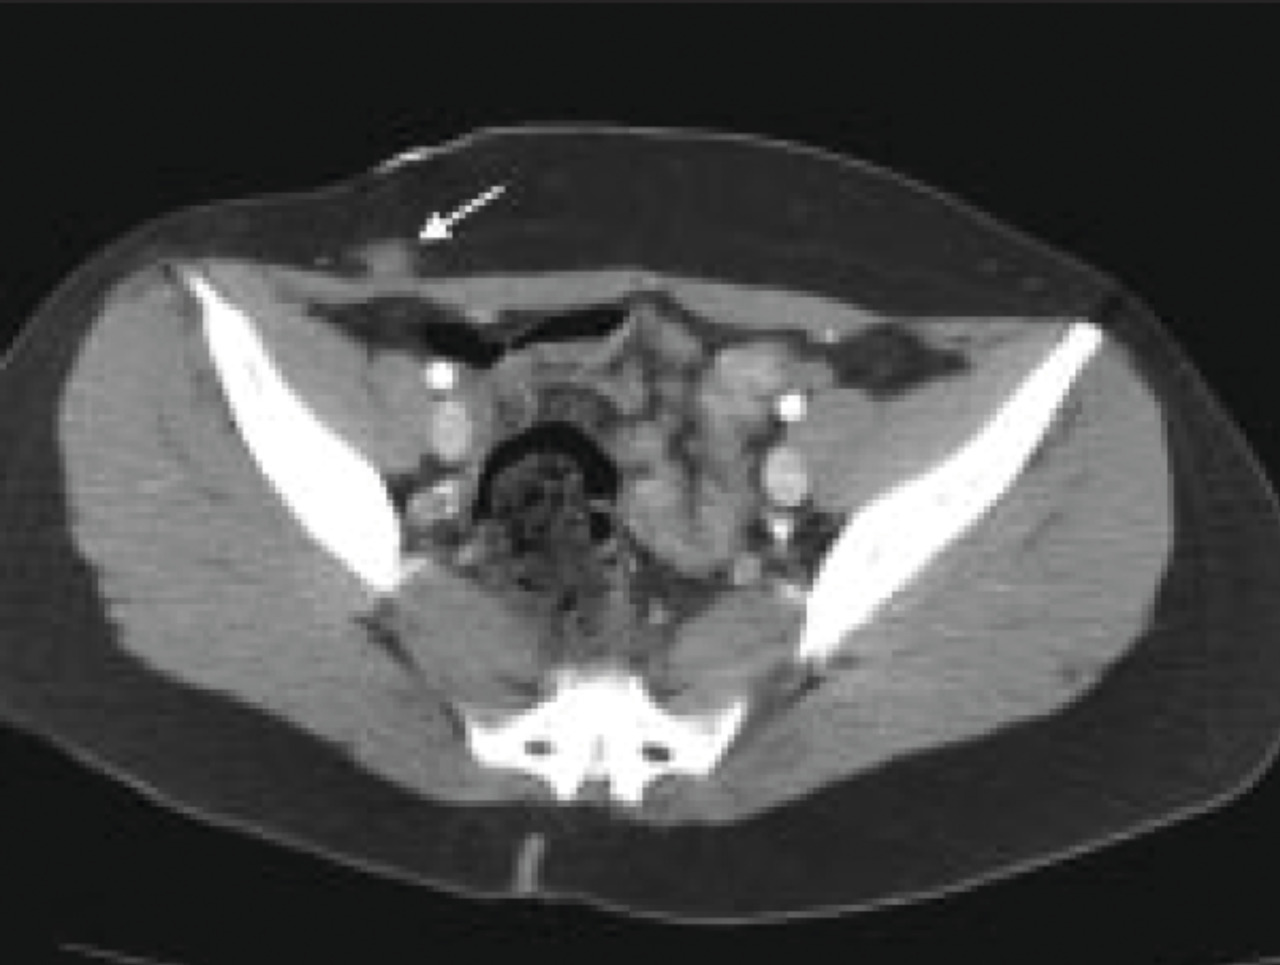

La tomodensitométrie n’est pas un bon examen pour diagnostiquer le nodule endométriosique pariétal dans la cicatrice de césarienne (fig 2).27 L’imagerie par résonance magnétique est plus adaptée pour l’exploration de la région pelvienne ; elle permet de rechercher une endométriose pelvienne dans le même temps qu’elle détermine les dimensions et la localisation précise du nodule endométriosique dans la paroi (fig. 3).30, 31